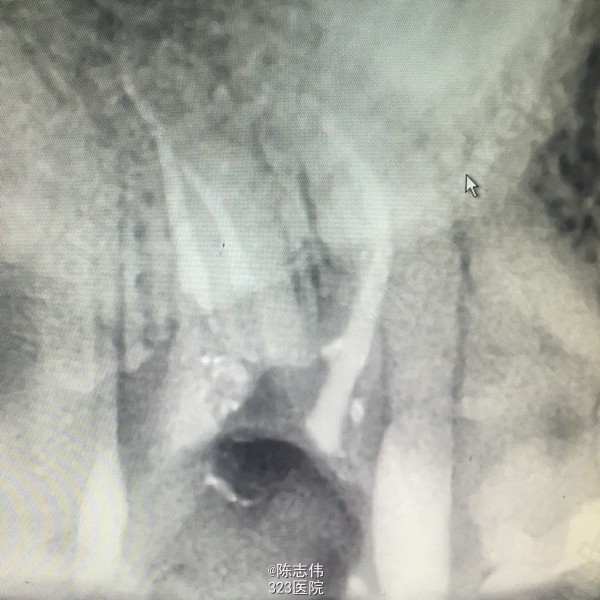

- 王凌回复美雅:根管很漂亮

- 美雅回复张景元:谢谢分享,45是不是稍微有点欠充呢?而试尖片看起来是不是有点超啊

- 张景元回复宋伟颉:谢谢分享这么完整的病例!根管治疗做得很漂亮,讲解也很到位,个人觉得根管之后还是需要进行冠修复,才能保证咬合功能不受太多影响!

根管做的好漂亮啊,佩服啊!

已做冠修复,只不过没有照照片